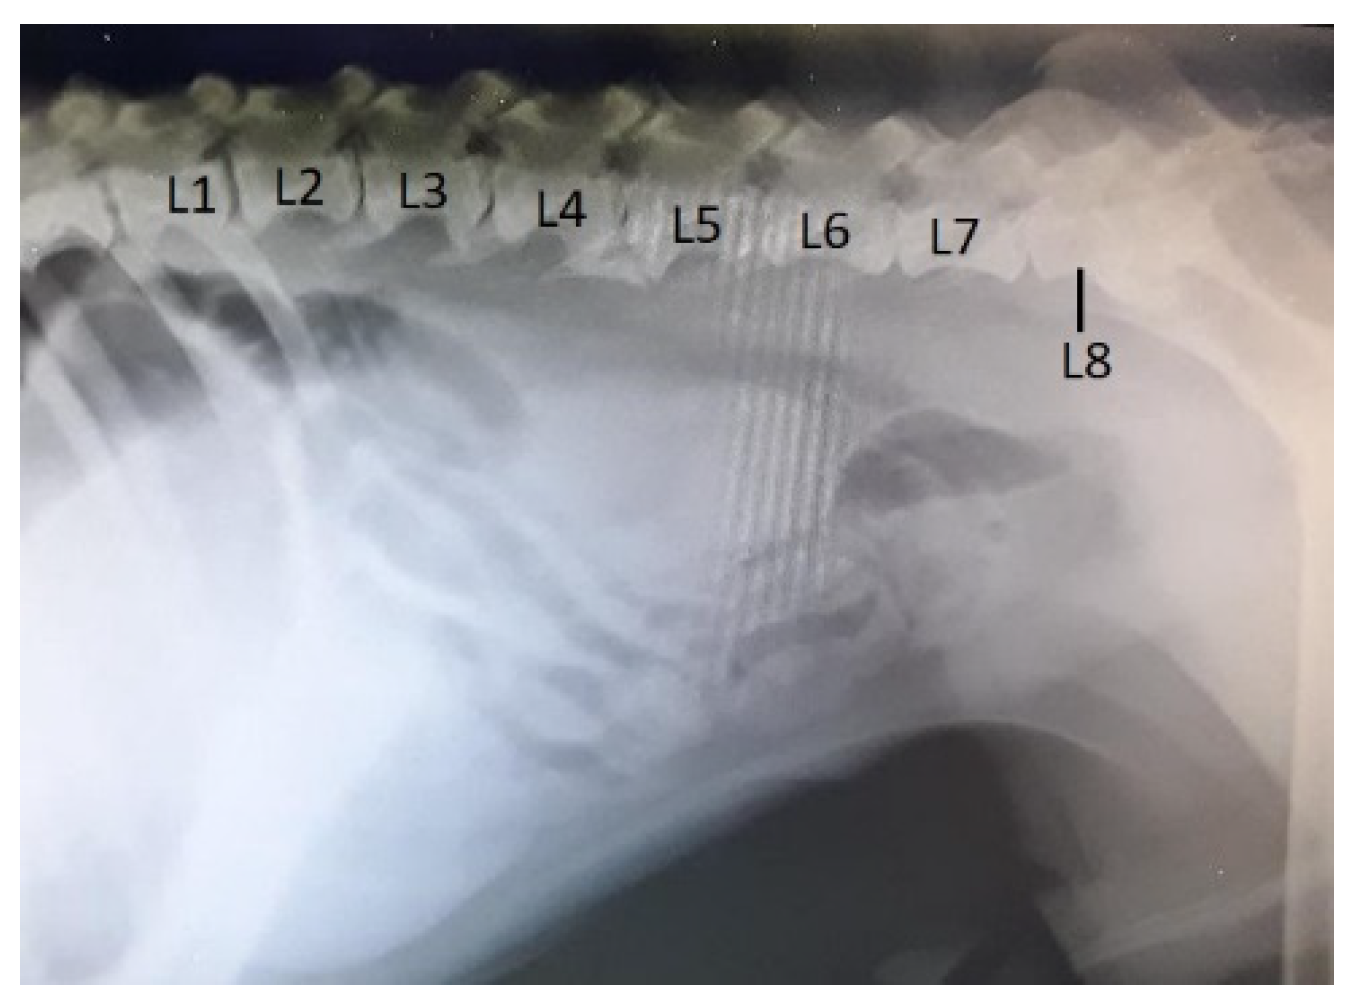

In dogs, among various pathologies, radiologically we identified transitional vertebrae in the lumbosacral junction, having the specific conformation of a lumbar vertebra (supernumerary vertebra) or fused more or less with the sacrum (sacralisation). Three animals had 8 lumbar vertebrae, the last one (L8) being generally shorter (Figure 11, Figure 12), two of them presenting also the sacralisation of L8. In the other dog has been observed the sacralisation of the 7th lumbar vertebra. In all cases the sacralisation was partial and asymmetric, a transverse process having a more appropriate shape to that of a normal one, the other being fused with the sacral wing and taking contact with the iliac wing (Figure 12).

Figure 11. Boxer dog, male, 6 years – supernumerary and transitional lumbo-sacral vertebra (L8), lateral view: shortening and sacralisation of L8; L1-L7 – lumbar vertebrae 1-7.

Preprints 91911 g011